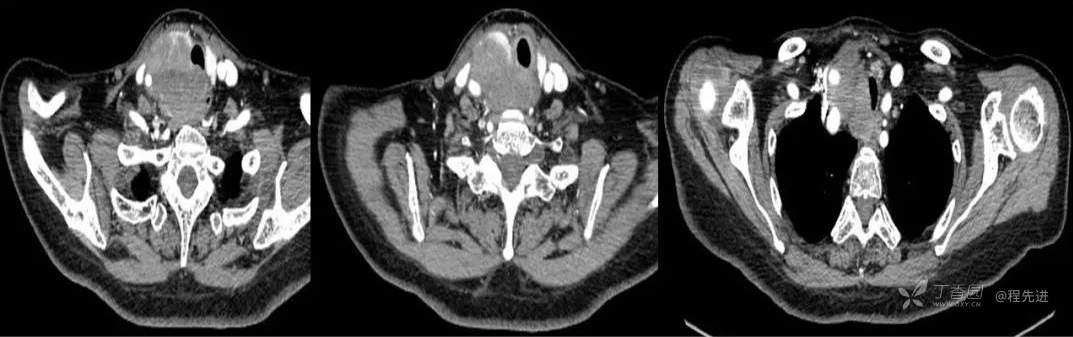

CT

增强